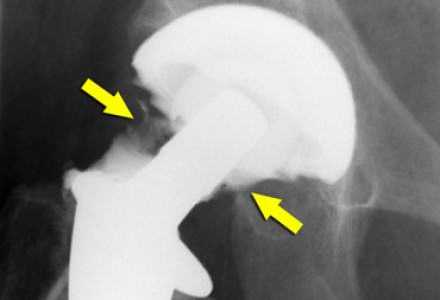

Когда возникают осложнения

Выраженная деформация суставных поверхностей костей, активные физические нагрузки и молодой возраст пациента повышают риск развития осложнений. Прогнозы на ближайшие несколько лет после качественно проведенной операции при использовании современных протезов довольно благоприятные даже при наличии факторов риска. При неблагоприятном течении часто развивается нестабильность и последующая протрузия компонентов эндопротеза.